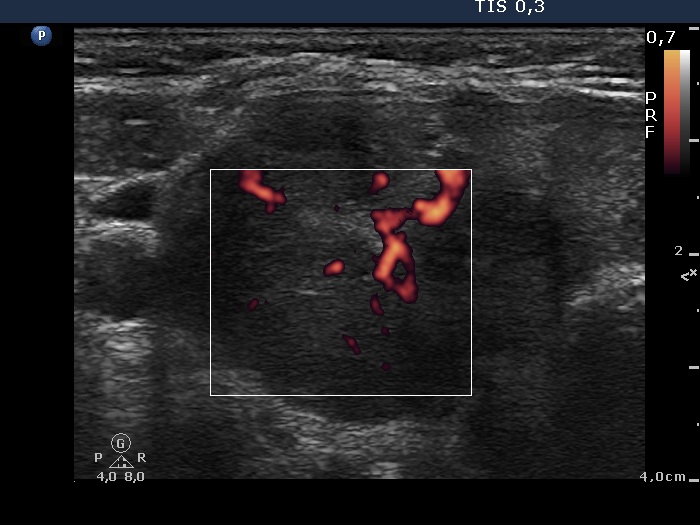

Consecutively operated patients with autoimmune thyroid disease - case 53 (495) (ultrasonographic picture 5)

Right lobe, transverse view, color Doppler mode.